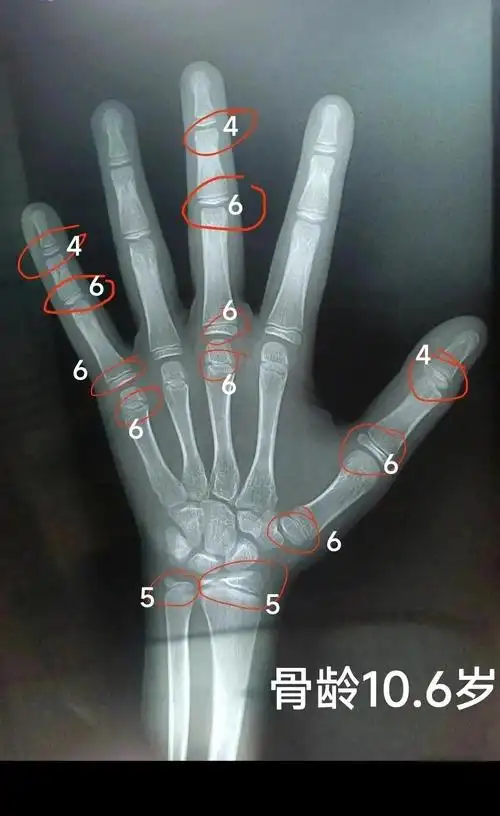

骨龄,简单来说,就是骨骼的年龄,它可是孩子生长发育的小小"晴雨表"

骨龄与年龄差多少算正常?影响长高吗?